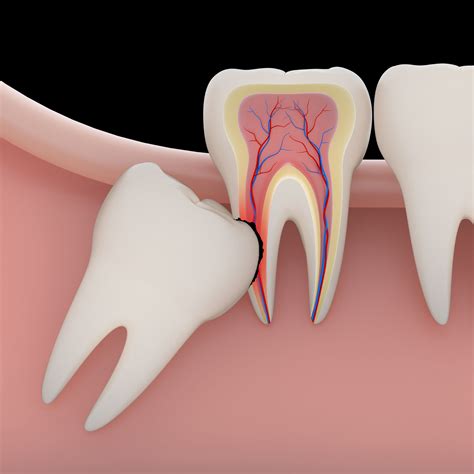

• Impacted Wisdom Teeth: Teeth that grow horizontally or at an angle, pushing against the roots of healthy, neighboring second molars.

• Cyst or Tumor Formation: Sometimes, fluid-filled sacs form around an impacted wisdom tooth, which can damage the jawbone and surrounding nerves if not removed promptly.